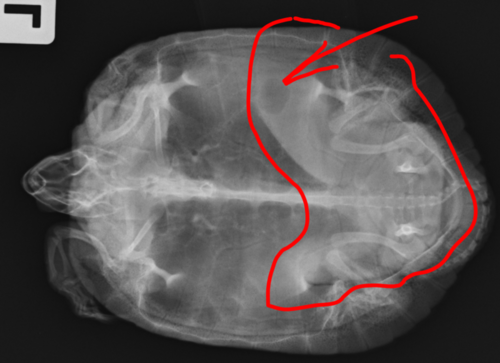

Антон123 Ваше имя: Антон Локация: Москва Опубликовано: 7 апреля 2022 Автор Опубликовано: 7 апреля 2022 (изменено) А нет. Шприц на 1мл. 50 делений. Вот 2,5 таких деления. Получается 0,02*2,5=0,05 И! Забыл написать в самом начале. Пару дней назад черепаха зависла не шевелясь в воде с открытым ртом и так и висела. А когда доставал ее на сушу, она бодро бежала назад в воду. И было ощущение, что она не может уходить на дно Также на самом нижнем рентгеновском снимке мне кажется что-то не то в нижней части черепахи. Изменено 7 апреля 2022 пользователем Антон123

Консультанты moth Ваше имя: Мария Локация: Москва Опубликовано: 8 апреля 2022 Консультанты Опубликовано: 8 апреля 2022 @Антон123 нет, Вы неправильно считаете 0.02 нужно умножить на количество маленьких делений, т.е. 0.02+12.5=0.25 т.е. Элеовит Вам нужно набрать по середине между 10 и 20 на шкале На рентгене это скорее всего скопление газов